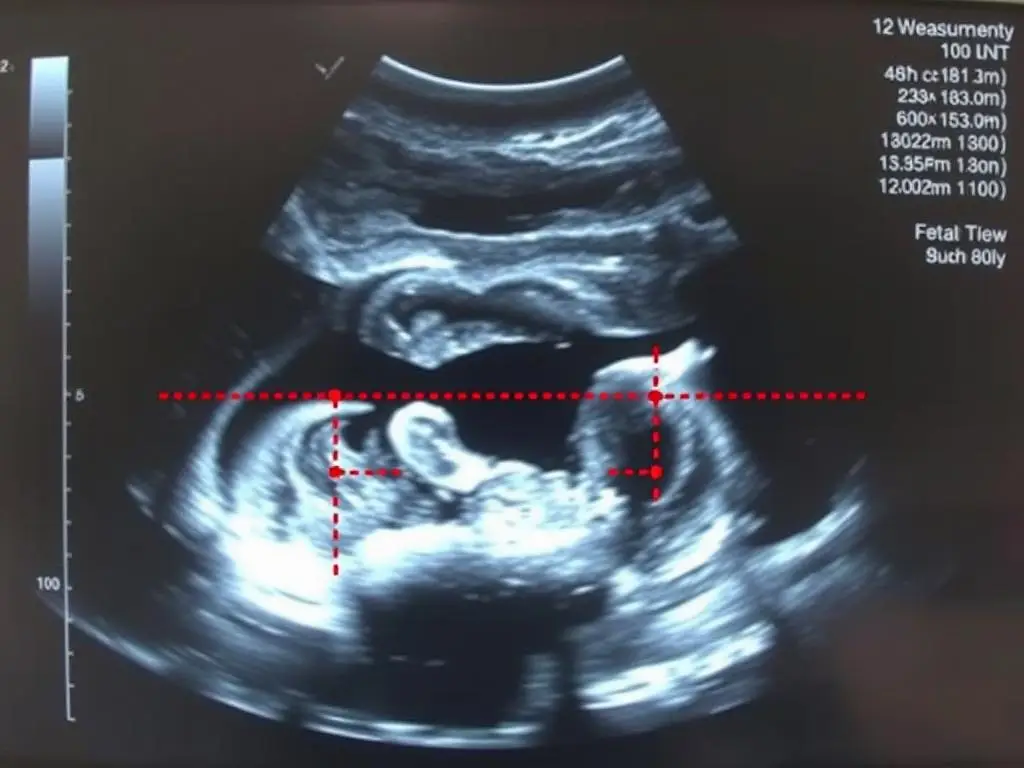

Badanie USG w 12 tygodniu ciąży – widoczny płód na monitorze

Między 11. a 14. tygodniem ciąży (najczęściej w 12. tygodniu) wykonuje się pierwsze obowiązkowe badanie ultrasonograficzne, nazywane USG genetycznym lub badaniem przezierności karkowej. Jest to jedno z najważniejszych badań prenatalnych, które pozwala ocenić prawidłowy rozwój dziecka oraz wykryć ewentualne nieprawidłowości [8].

Podczas USG w 12 tygodniu ciąży lekarz dokładnie ocenia budowę anatomiczną płodu, mierzy długość ciemieniowo-siedzeniową (CRL), która pozwala precyzyjnie określić wiek ciążowy i termin porodu. Sprawdza również bicie serca dziecka, ilość płynu owodniowego oraz położenie i strukturę łożyska [9].

Pomiar przezierności karkowej podczas USG genetycznego

Kluczowym elementem badania jest pomiar przezierności karkowej (NT), czyli gromadzenia się płynu pod skórą karku płodu. Zwiększona wartość tego parametru może wskazywać na podwyższone ryzyko wystąpienia wad genetycznych, takich jak zespół Downa, zespół Edwardsa czy zespół Pataua. Badanie to, w połączeniu z badaniami biochemicznymi krwi matki (test PAPP-A), tworzy tzw. test podwójny, który pozwala oszacować ryzyko wystąpienia najczęstszych aberracji chromosomowych [10].

USG w 12 tygodniu ciąży umożliwia również ocenę rozwoju narządów wewnętrznych dziecka. Lekarz sprawdza budowę serca, mózgu, kręgosłupa, nerek, pęcherza moczowego oraz kończyn. Widoczne są już palce u rąk i stóp, które można policzyć podczas badania. Dziecko wykonuje spontaniczne ruchy, choć matka jeszcze ich nie odczuwa [11].